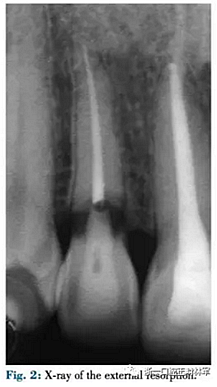

42歲需要牙頸部修復的女性患者(圖1)。16歲時上頜側切牙外傷史,根管治療時有牙外吸收(圖2)。由于其存在充足的牙體組織因此決定使用修復手段而非種植。修復方式取決于暴露的吸收邊緣,傳統(tǒng)多使用冠延長術,但在微笑美學區(qū)較困難。因此在第一階段進行正畸緩慢牽引來排齊并增加軟組織量,后期結合纖維環(huán)切術進行快速牽引牙根,使用舌側矯治器。